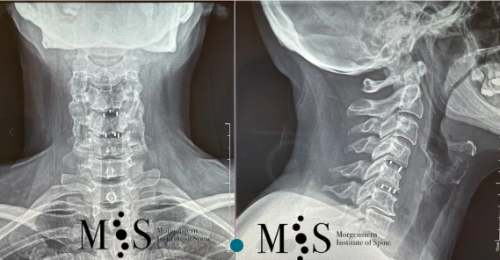

Post-operative X-rays showing an interbody cage at two separate cervical disks after placement with endoscopic fusion surgery

of the cervical spine and was discharged from the hospital in less than 24 hours after surgery.

X-ray in A/P (left figure) and lateral (right figure) figures of a titanium

interbody cage placed at level C5/C6 with endoscopic surgery

Clinical case example

This 49 years-old patient presented with a migrated cervical herniation at level C4/C5 and an unstable disk at C5/C6. En endoscopic cervical decompression was performed to remove the herniation and two intervertebral cages were placed endoscopically using a a skin incision of just 2 cm length. Post-operatively, the patient recovered very quickly and was discharged from the hospital within a day after surgery.